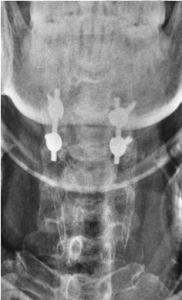

X-Ray of his cervical spine showed extensive ossification of posterior longitudinal ligament (OPLL) extending from C2 to C6 segments.

There was also presence of Diffuse Idiopathic Skeletal Hyperostosis (DISH). MRI of this cervical spine showed severe narrowing of spinal canal at C3-4 segment with cord compression and cord oedema. He was diagnosed as having severe central cord syndrome.

Because of the presence of proprioception in his right foot, the injury is deemed to be incomplete tetraplegia which implies the potential for recovery. The surgery consisted of C3 and C4 laminectomies to decompress the spinal cord. In view of the instability, C3 and C4 lateral mass plating were also performed to provide instrumented fusion on the 5th post injury day.